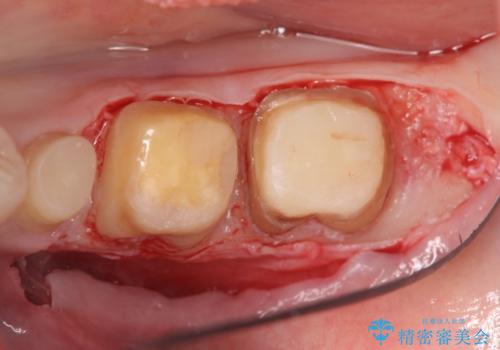

虫歯を除去すると、歯ぐきよりも深い虫歯であることが判明したため歯周外科を行い問題を解決していきます。

歯ぐきの炎症は虫歯や歯周病の再発原因となるため歯周外科による解決が望ましいです。